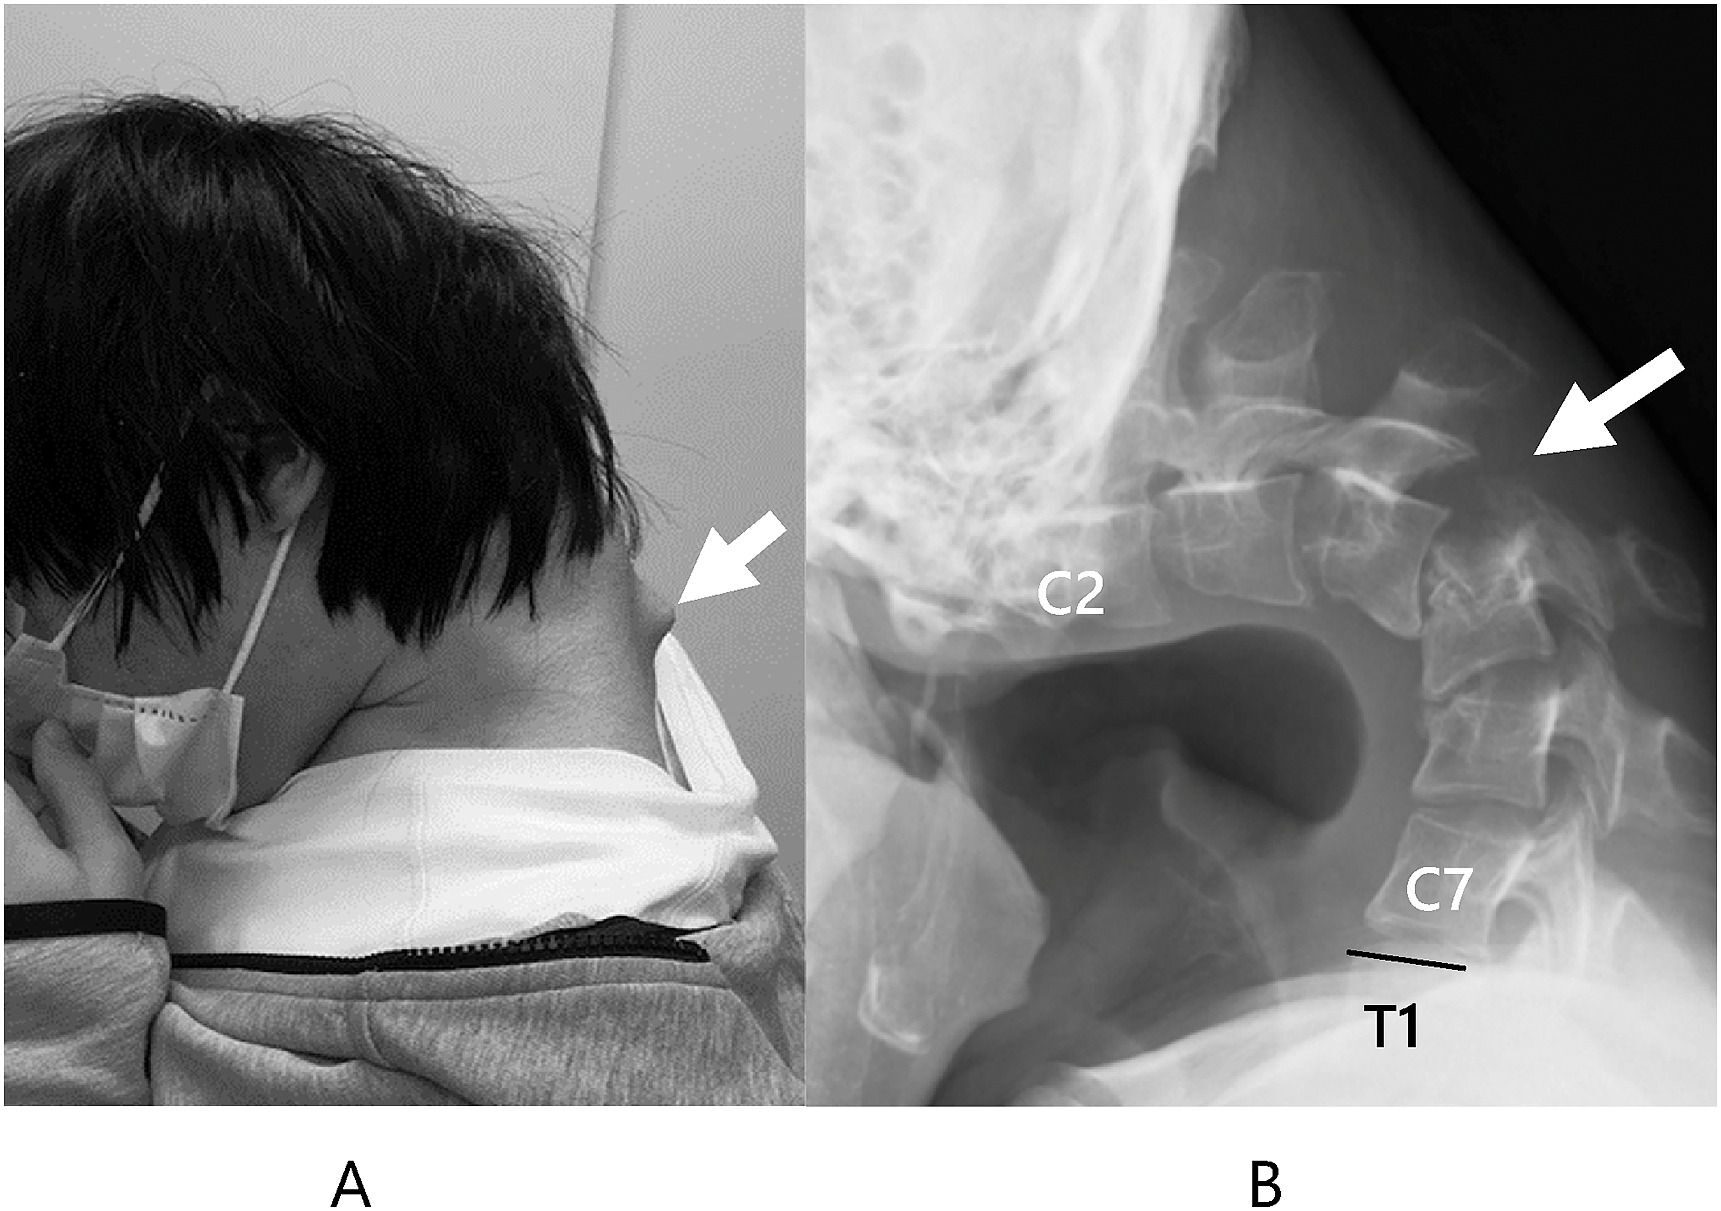

មានករណីដ៏មិននឹកស្មានរបស់បុរសជនជាតិជប៉ុនវ័យ ២៥ ឆ្នាំម្នាក់ ដែលឱនលេងហ្គេមទូរស័ព្ទជាប្រចាំ បណ្តាលឱ្យខូចសាច់ដុំក រហូតដល់ងើបមុខលែងកើត លេបបាយក៏មិនបាន ព្រោះកញ្ជឹង-កបត់ចូលគ្នាគួរឱ្យខ្លាច។

តាមរយៈ JOS Case Reports ក្នុងឆ្នាំ ២០២៣ បានឱ្យដឹងថា កាលនៅក្មេងបុរសនេះមិនសូវជាមានមិត្តភក្តិឡើយ ព្រោះគេចូលចិត្តធ្វើបាបមើលងាយ ទើបផ្តាច់ខ្លួននៅតែឯង ហើយចំណាយពេលវេលាតែជាមួយនឹងហ្គេមទូរស័ព្ទ។ លុះក្រោយមក ក៏កើតការទន់ឆ្អឹងកបត់ចូលគ្នា ដែលគេហៅថា (Dropped Head Syndrome) ធ្វើឱ្យខូចទ្រង់ទ្រាយ បណ្តាលឱ្យងើបក្បាលក៏លែងកើត ពិបាកទទួលទានអាហារ ទម្ងន់ថយចុះយ៉ាងលឿន ដោយសារតែការឱនលេងហ្គេមទាំងយប់ទាំងថ្ងៃ។

ដំបូងឡើយគ្រូពេទ្យបានព្យាយាមប្រើឧបករណ៍ដើម្បីទាញកបុរសនេះចេញពីគ្នាវិញ តែមើលទៅហាក់ដូចជាមានការឈឺខ្លាំង ទើបក្រោយមកក៏បានធ្វើការវះកាត់វិញ ហើយក្រោយពីធ្វើការវះកាត់មួយឆ្នាំ បុរសនេះក៏ត្រឡប់មកដូចដើមវិញ។ ដោយឡែក គ្រូពេទ្យបានដាស់តឿនចំពោះមហាជន ឱ្យប្រយ័ត្នចំពោះរឿងប្រើទូរស័ព្ទ ជាពិសេសគឺក្រុមក្មេងៗ និង យុវជនដែលចូលចិត្តឱនលេងហ្គេមជាប្រចាំ៕